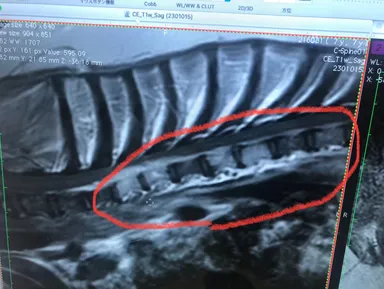

(2)

※腫瘍部を拡大して画像です。縦の白い柱が、腫瘍に侵されてしまった骨です。

左側、白い骨の上部に細長い雲の様に見える物も腫瘍です。